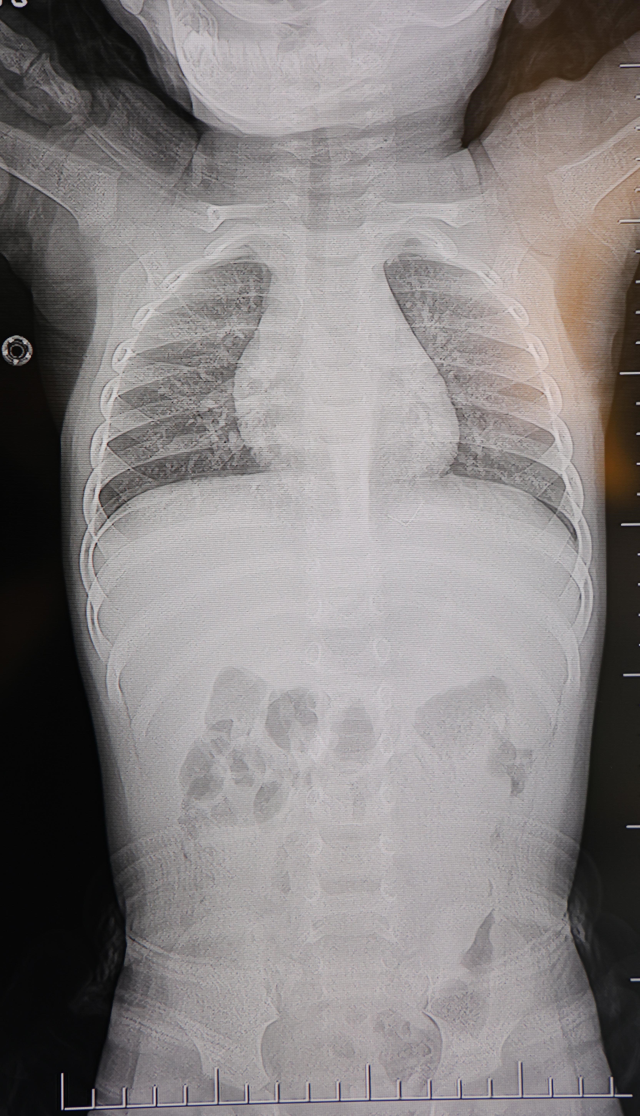

Kahramanmaraş'ta sırt üstü yatmak istemeyen ve yatırıldığında ağlayan ve huzursuzluk çıkaran 1 yaşındaki bebeğin sırtından akciğer zarına doğru ilerleyen 2 santimetrelik zımba teli çıkarıldı. Vakayla ilgili konuşan Prof. Dr. İdris Altun, "Cisim alınmasaydı enfeksiyon gelişebilir omurilik kanalında ciddi hasarlar oluşabilirdi" dedi.

- 1 yaşındaki bir bebeğin sırtında, omurilik kanalına yakın ve akciğer zarına doğru ilerleyen yaklaşık 2 santimetre uzunluğunda metal bir tel tespit edildi.

Ailenin son olarak başvurduğu hastanede yapılan tetkiklerde, yabancı cismin cilt altında, omurilik kanalına yakın bir bölgede olduğu ve akciğer zarına doğru ilerlediği belirlendi.